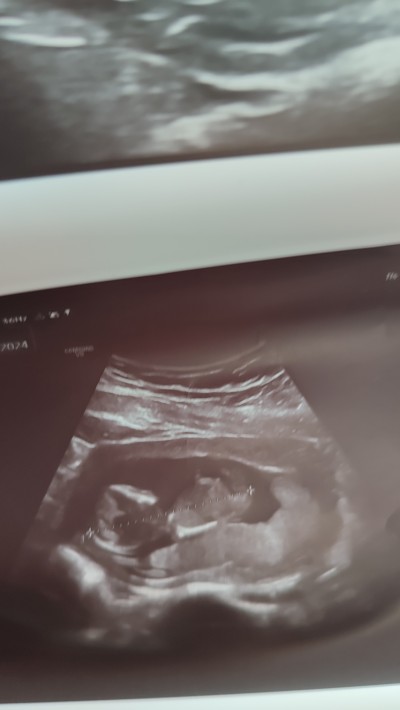

12+5 cinsiyet tahmini yapabilen arkadaşlarım var mı merak ediyorum doktor daha erken dedi

Gebelik haftası 12+5